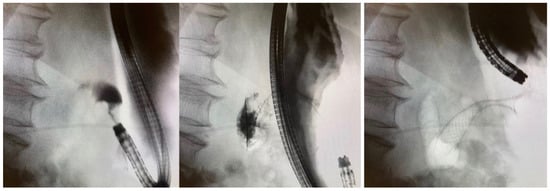

4. Pre-Procedural Patient Evaluation

5.3. Endoluminal Insertion of SEMS